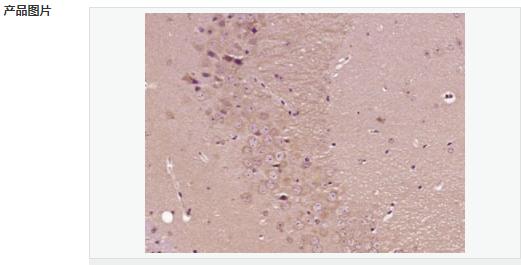

image.png